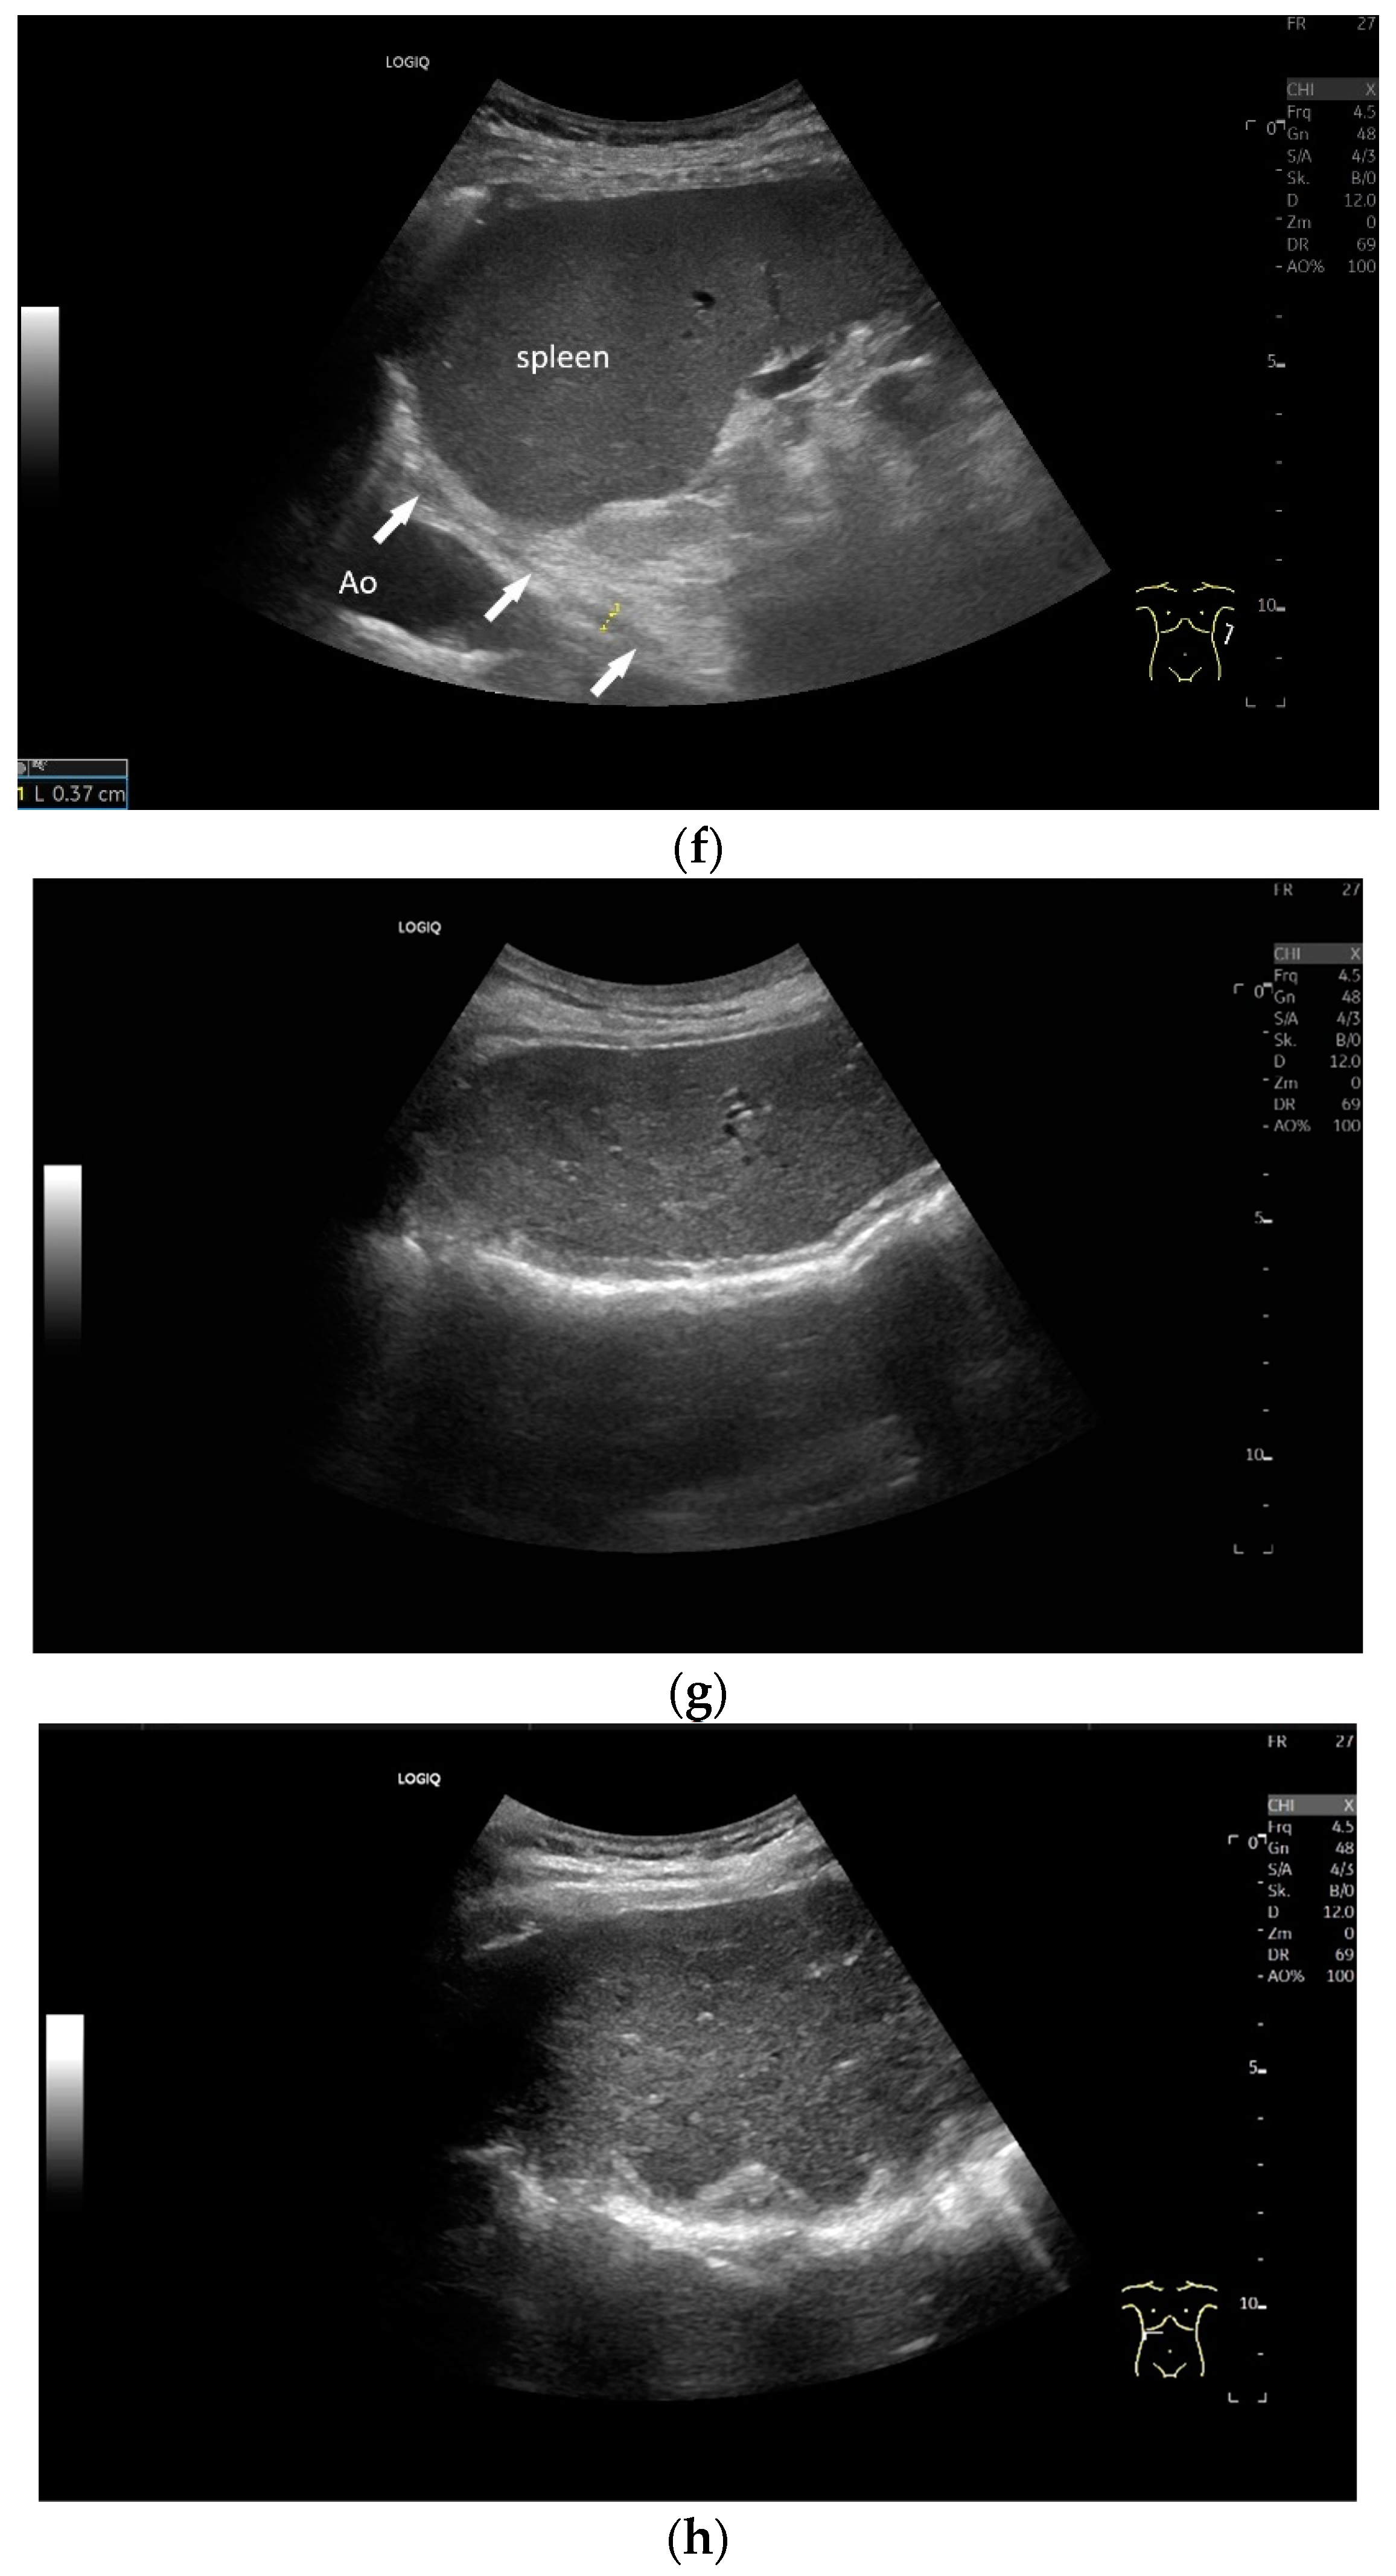

Subxiphoid: The diaphragm can be positioned directly subxiphoidally with a slightly sagittal transducer position on both sides next to the attachment to the sternum. The diaphragm limb can be demarcated to the right in the epigastrium in cross section between the aorta and the inferior vena cava. However, this is primarily of differential diagnostic importance, e.g., in relation to lymphomas, not for the actual assessment of the diaphragm (Figure 6).